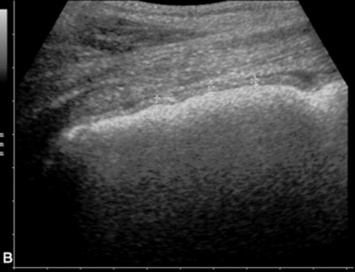

Ultrasound evaluation of horses with abdominal pain (colic) provides a rapid method to identify abnormalities within the gastrointestinal tract. Distention of the small intestine to a diameter greater than 5 cm has been strongly associated with strangulating or obstructing lesions19 (Fig. 32-11). In foals with intussusception, the small intestine appears enlarged and there is generally distended small intestine orad to the lesion; however, at the site of the intussusception there is a normal-appearing small intestinal wall (intussuscipiens) surrounded by a larger structure that appears to surround the inner small intestinal wall (called the intussusceptum)19 (Fig. 32-12). Large colon torsion occurs when the large colon rotates 360 degrees or more around the root of the mesentery to cause occlusion of venous drainage while maintaining arterial flow. This causes the wall to become thick and edematous. If ultrasound is performed in the cranioventral abdomen, just caudal to the xiphoid process, then a colon wall size greater than 9 mm is 100% specific for a large colon torsion21 (Fig. 32-13). A large colon displacement would have minimal to no vascular compromise, so it would be an ultrasound diagnosis based on exclusion. Chronic displacements did have a mild amount of edema in the colon wall, causing the size to be approximately 7 mm thick but never greater than 9 mm in the one study described.21 The colon and small intestinal wall will also become thick with inflammation. Small intestinal wall thickness greater than 4 mm is indicative of inflammation.19 The right dorsal colon can be imaged in the right tenth to twelfth intercostal space around the region of the costochondral junction, and a focal wall thickness of 9 to 12 mm has been identified with right dorsal colitis.23

image

Fig. 32-11 Transabdominal ultrasonographic image of a 6-year-old thoroughbred gelding with acute onset of colic. The small intestine is 7 cm in diameter and was noted to have minimal to no contractility. This is consistent for mechanical ileus. A strangulating lipoma was identified at surgery.

Courtesy of Cornell University.